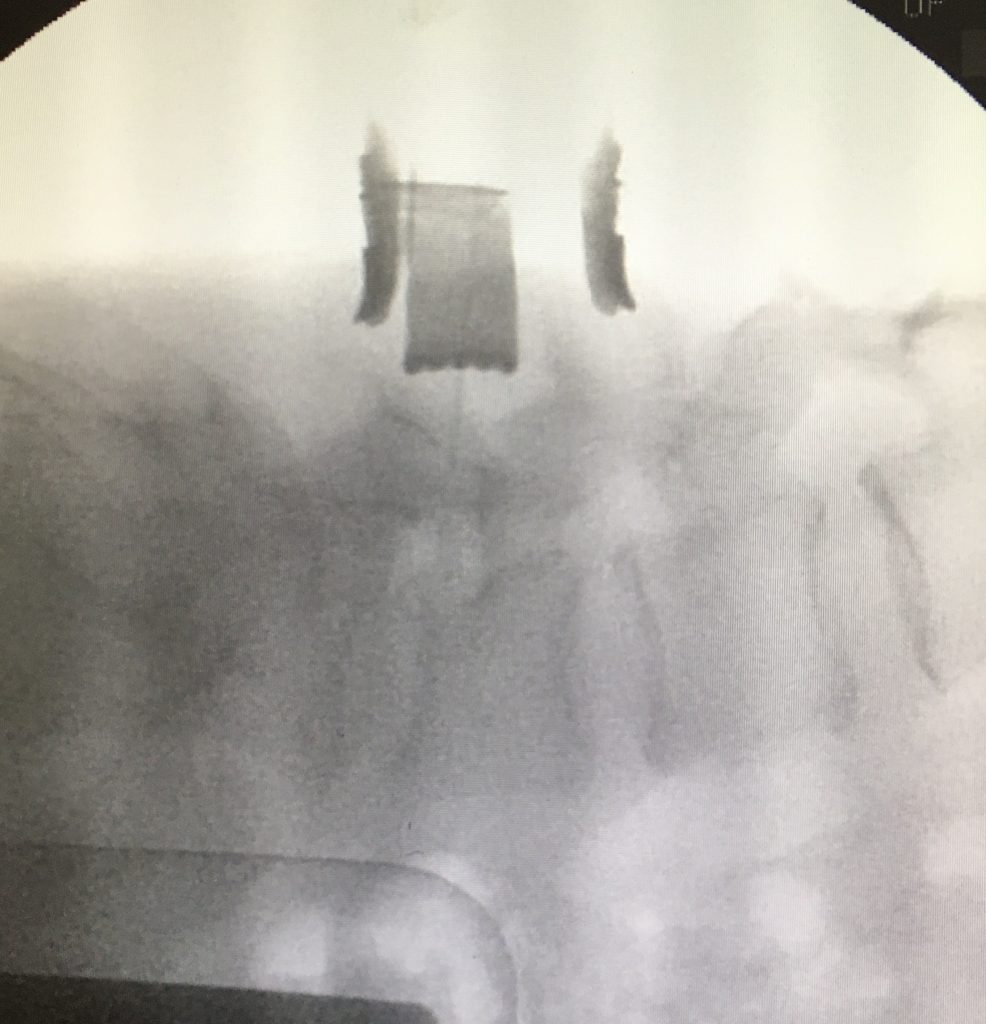

Existen múltiples técnicas para conseguir la fusión de la columna lumbar. La artrodesis posterior instrumentada es la técnica más habitual. Consiste en colocar tornillos de fijación en las vértebras, y un implante a nivel del disco (caja intervertebral), lo que permite liberar nervios en el canal espinal y reconstruir la columna de un modo muy efectivo. La técnica habitual se denomina TLIF (transforaminal lumbar interbody fusion). Esta técnica también puede realizarse de forma mínimamente invasiva.

En determinados pacientes el abordaje para colocar la caja puede ser por vía anterior; la técnica se denomina ALIF (anterior lumbar interbody fusion).

Esta técnica permite en pacientes seleccionados respectar la musculatura lumbar y acortando los tiempos de recuperación.Finalmente, esta fusión se puede realizar de manera mínimamente invasiva, con una pequeña incisión a través del lateral del abdomen, lo que se denomina técnica XLIF u OLIF (extrem lateral lumbar interbody fusion).Técnica mínimamente invasiva, utilizada para favorecer la reconstrucción vertebral y fusión en deformidad y casos con afectación de múltiples discos.